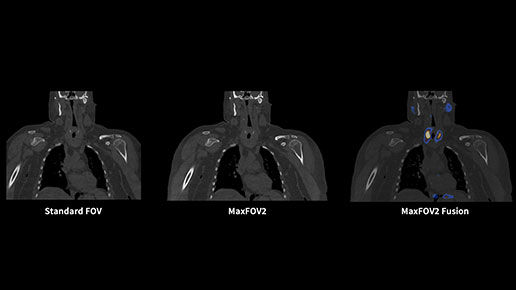

MaxFOV2* extends the display field of view (DFOV) from 50 cm to 75 cm¹⁴

When body size or positioning causes portions of the patient to extend outside the scan field of view, MaxFOV2's AI algorithm overcomes this, enabling the visualization of the patient's whole anatomy.

MaxFOV2-feature03-desktop

Aurora's 75 cm-wide CT bore opens up more space to high BMI patients for a comfortable scanning experience. The 75 cm CT display field of view with MaxFOV2* enables the visualization of high BMI patient's whole anatomy.¹⁴

14. The image quality for the area outside the standard 50 cm scan field does not meet the image quality specifications shown in the technical data sheet and image artifacts may appear, depending on the anatomy scanned.